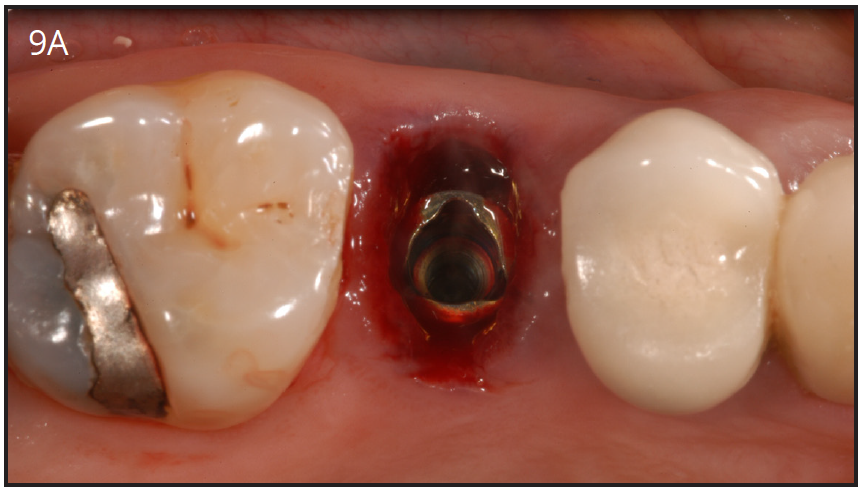

The implant platform can also have different shapes. It can be internal connection or external connection with the abutment. The original Branemak system had an external connection. The internal connection platform is the most preferred today in dental practices due to ease of handling. (Figures 9A-C)

Figure 9A – Internal connection implant system – implant placed

post-extraction

Figure 9A